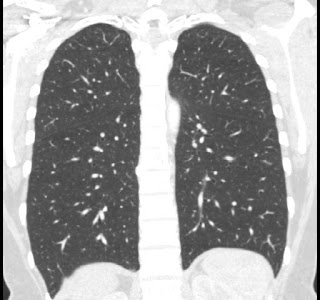

40 year old female. Breast implants 17 years ago, most likely Dow Corning. Symptoms from upper body for 6-7 years. Pain in breasts, ribs, back, neck. Skin rash. Headache and dizziness, weakness, numbness and vision disturbing. Sudden sleep episodes. Painful lymph-notes. These images are from 2010 and diagnose results were "No findings". Patient is scheduled for explantation in mid Feb. 2012